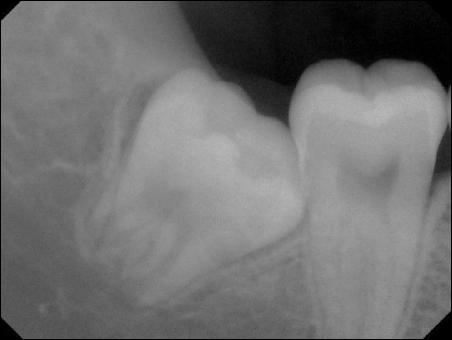

典型的垂直阻生狀況